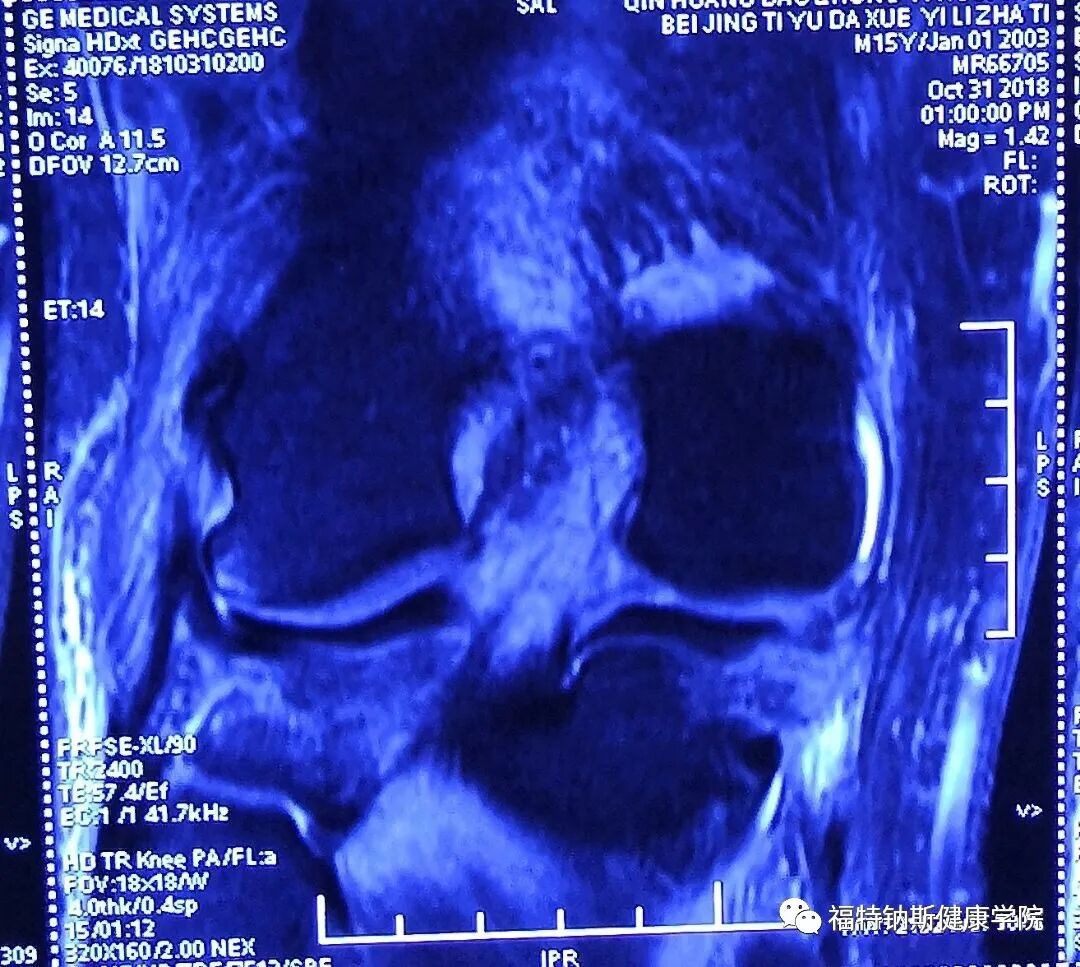

大家好,我是Dean,我是一名在美国执业的物理治疗师和运动损伤防护师。感谢美国南加州大学运动机能与物理治疗学系的邀请,我于2012年随团队一起来到中国开展物理治疗教育。 近年来我一直持续在中国与陈月博士福特钠斯团队合作开展一年两次的上、下肢运动康复的物理治疗继续教育课程。我的治疗和教学课程融合了运动损伤防护背景及物理治疗教育背景和受训经历,将使用手法技术重建活动范围和功能,并同时结合渐进性地运动功能训练。 我希望大家能从接下来的公众号的更文中有所收获。我的目标是以我自己这次严重的膝关节损伤为例,来展示一个在多种组织结构受损的损伤案例中,如何基于组织愈合速率来达到评估损伤,并推进康复的良好流程。这个膝关节受伤的案例中有三种不同的组织结构受损,它们对于治疗的方式及愈合时间的要求均是不同的。 Dean Caswell,PT, OCS, ATC, AT/L, CSCS 一、韧带评估测试(续) Ligament Testing Evaluation Continued LCL/FCL Attachment Sites:Origin lateral femoral epicondyle, joins the biceps femurs tendon before attaching to fibular head. 外侧副韧带/腓侧副韧带起止点:起于股骨外上髁;与股二头肌肌腱结合后止于腓骨小头 二、外侧副韧带损伤评估 0/0 继续观看 【大咖专栏】Dean博士教你如何系统评估膝关节运动损伤 LCL Palpation 外侧副韧带触诊 0/0 继续观看 【大咖专栏】Dean博士教你如何系统评估膝关节运动损伤 LCL Testing 外侧副韧带测试 1、外侧副韧带损伤常见于以下情况: Direct blow to the inside of the knee, such as during a football tackle 膝关节内侧直接受到横向的力,如足球当中飞铲 Quickly changing directions or pivoting on one foot, such as in soccer or basketball 在足球或篮球运动中快速变向或是脚部的扭转 Landing awkwardly from a jump, such as during volleyball or basketball 在排球或足球运动中,跳起后错误的落地 People may also note instability in their knee, particularly with side-to-side or pivoting activities. 人们通常感觉他们的膝关节不稳,尤其是横向不稳或是扭转活动时不稳 Isolated LCL tears are less common than other ligament injuries, such as medial collateral ligament (MCL) or anterior cruciate ligament (ACL) tears. They are most often seen in athletes and alongside other injuries, such as knee dislocations 单独的外侧副韧带撕裂相较于其他韧带(如内侧副韧带,前交叉韧带)并不常见。在运动员群体里常见这样的损伤,并且是伴随其他损伤出现的,比如膝关节脱臼。 2、LCL损伤分级 Grade1 Grade 1 lateral ligament sprain symptoms include tenderness on the outside of the knee over the ligament. Usually, there will be little or no swelling. When the knee is bent to 30 degrees and force applied to the inside of the knee which puts the ligament under stress, pain is felt but there is no joint laxity. This is known as the varus stress test. 一级的外侧副韧带拉伤症状包括膝关节外侧韧带上方疼痛;通常可见少许肿胀或无肿胀;膝关节屈曲30度后,由内侧向外施加一个横向的力使外侧副韧带受力,可激惹痛感,但没有松弛感,这个测试被称作内翻试验。 Grade2 With a grade 2 LCL sprain, you will have significant tenderness on the outside of your knee, over the lateral ligament. You will likely have some swelling. A varus stress test will indicate pain and some laxity in your joint, although there is a definite endpoint indicating the ligament is still intact. 二级外侧副韧带拉伤症状包括明显的膝关节外侧疼痛,韧带上方疼痛;可见肿胀;内翻应力测试可见激惹痛与关节松弛感,但同时可见关节终末感由此可推断韧带还是连着的,没有完全断裂。 Grade3 A grade 3 lateral ligament sprain is a complete tear of the ligament. Pain can vary and may be actually less than a grade 2 sprain. When stressing the knee there is significant joint laxity and you may have a very unstable knee. 三级外侧副韧带拉伤是韧带安全撕裂,其痛感可以且很可能弱与二级拉伤;内翻应力测试可见明显关节松弛感开合感,关节极其不稳定。 3、Dean膝关节外侧副韧带试验结果 Findings of LCL TEST: Dean’s Knee 1、Palpation 触诊: Tenderness at origin/insertion sites, minimal to no pain at center 韧带起止点均有明显痛感;韧带中部轻度痛感或无痛感 Pain Scale to palpation with light touch 3/10 轻触痛感评分3/10 2、Ligament test 韧带试验: Significant movement at joint with laxity at ligament 明显的关节开合感,及韧带松弛感 No Significant pain with test 试验未见痛感 三、Cinical Reasoning (Previous Blog) 临床推断: (前文) Q&A Q1 Based on MRI below what would you grade MCL Tear? 基于下面的核磁结果请为患者内侧副韧带损伤分级: A1 Grade 3 Tear 三级撕裂: highlighted area of MCL with continuous highlight across length of tendon area. 内侧副韧带可见高亮信号;肌腱走向上连续的高亮信号 Q2 What is the current rehabilitation concept regarding repair for MCL tears? 现在针对内侧副韧带的损伤康复有哪些方面需要考虑? A2 The consensus is that isolated MCL tears rarely require operative repair, while treatment of severe combined ruptures of the MCL and anterior cruciate ligament or PCL would require reconstruction. [1] A study found that nonoperative and operative treatments of medial collateral ligament injuries lead to equally good results. Another indication for surgical intervention would be persistent instability, with surgery consisting of tissue repair and imbrication. Often, reinforcement with an allograft is necessary. 共识认为单独的内侧副韧带撕裂一般很少需要手术修复,然而严重的内侧副韧带结合前交叉韧带或后交叉韧带撕裂的治疗需要手术重建。 [1]有研究表明对于内侧副韧带的治疗手术与非手术对比均可见较好的疗效。另一个手术的指征是连续性不稳,手术包括组织重建和覆盖。通常来说,用自体移植物进行加固是很有必要的。 Grade 1 and 2 sprains are routinely treated non-operatively. They may be braced with a knee sleeve or a double-upright hinged knee orthosis, individualized to the patient's discomfort. Crutches are only necessary for a few days. These injuries represent incomplete tears and allow for a rapid return to activities. 一级二级的拉伤通常会选择保守治疗;患者可以个性化需求佩戴如套袖型双铰链类型的支具。也可能需要患者拄拐几天。这类的损伤意味着韧带的不完全撕裂,及较为快速的活动恢复 Historically, grade 3 tears were treated operatively but currently are routinely treated nonoperatively. In the past, nonoperative treatment meant a long leg cast. Currently, bracing with a hinged knee orthosis is common. Some authors recommend immediate braced increase in range of motion (ROM), while others prefer waiting up to 6 weeks with the knee at 30° of flexion. Crutches are usually necessary for 1-2 weeks. 早期的三级拉伤通常采用手术治疗,但现今保守治疗也是常见的选择。在过去,非手术干预意味着长时间的石膏固定,但现今通过铰链式的膝关节支具比较常见。一些作者认为受伤后即刻佩戴支具可以提高关节活动度,另一些人认为6周后待患侧可以屈曲30度后佩戴支具更佳。拐杖通常在早期的1-2周内是必须的 People with grade 1 and 2 injuries usually return to play within 2-3 weeks. People with grade 3 injuries frequently require 6 or more weeks before a return to play. 一级二级患者通常可在2-3周后恢复体育运动,三级患者通常需要6周以上的时间返回体育运动 [1] Dale KM, Bailey JR, Moorman CT 3rd. Surgical Management and Treatment of the Anterior Cruciate Ligament/Medial Collateral Ligament Injured Knee. Clin Sports Med. 2017 Jan. 36 (1):87-103. Q3 What other structures do you see potential injury to in the below MRI Images? 除内侧副韧带外还有哪些组织可能受到了损伤 A3 Highlights at medial and lateral hamstring tendons 内侧和外侧腘绳肌肌腱可见高亮信号 Highlights at medial & lateral meniscus 内侧和外侧半月板可见高亮信号 MRI影像: 持续更新中,敬请期待!